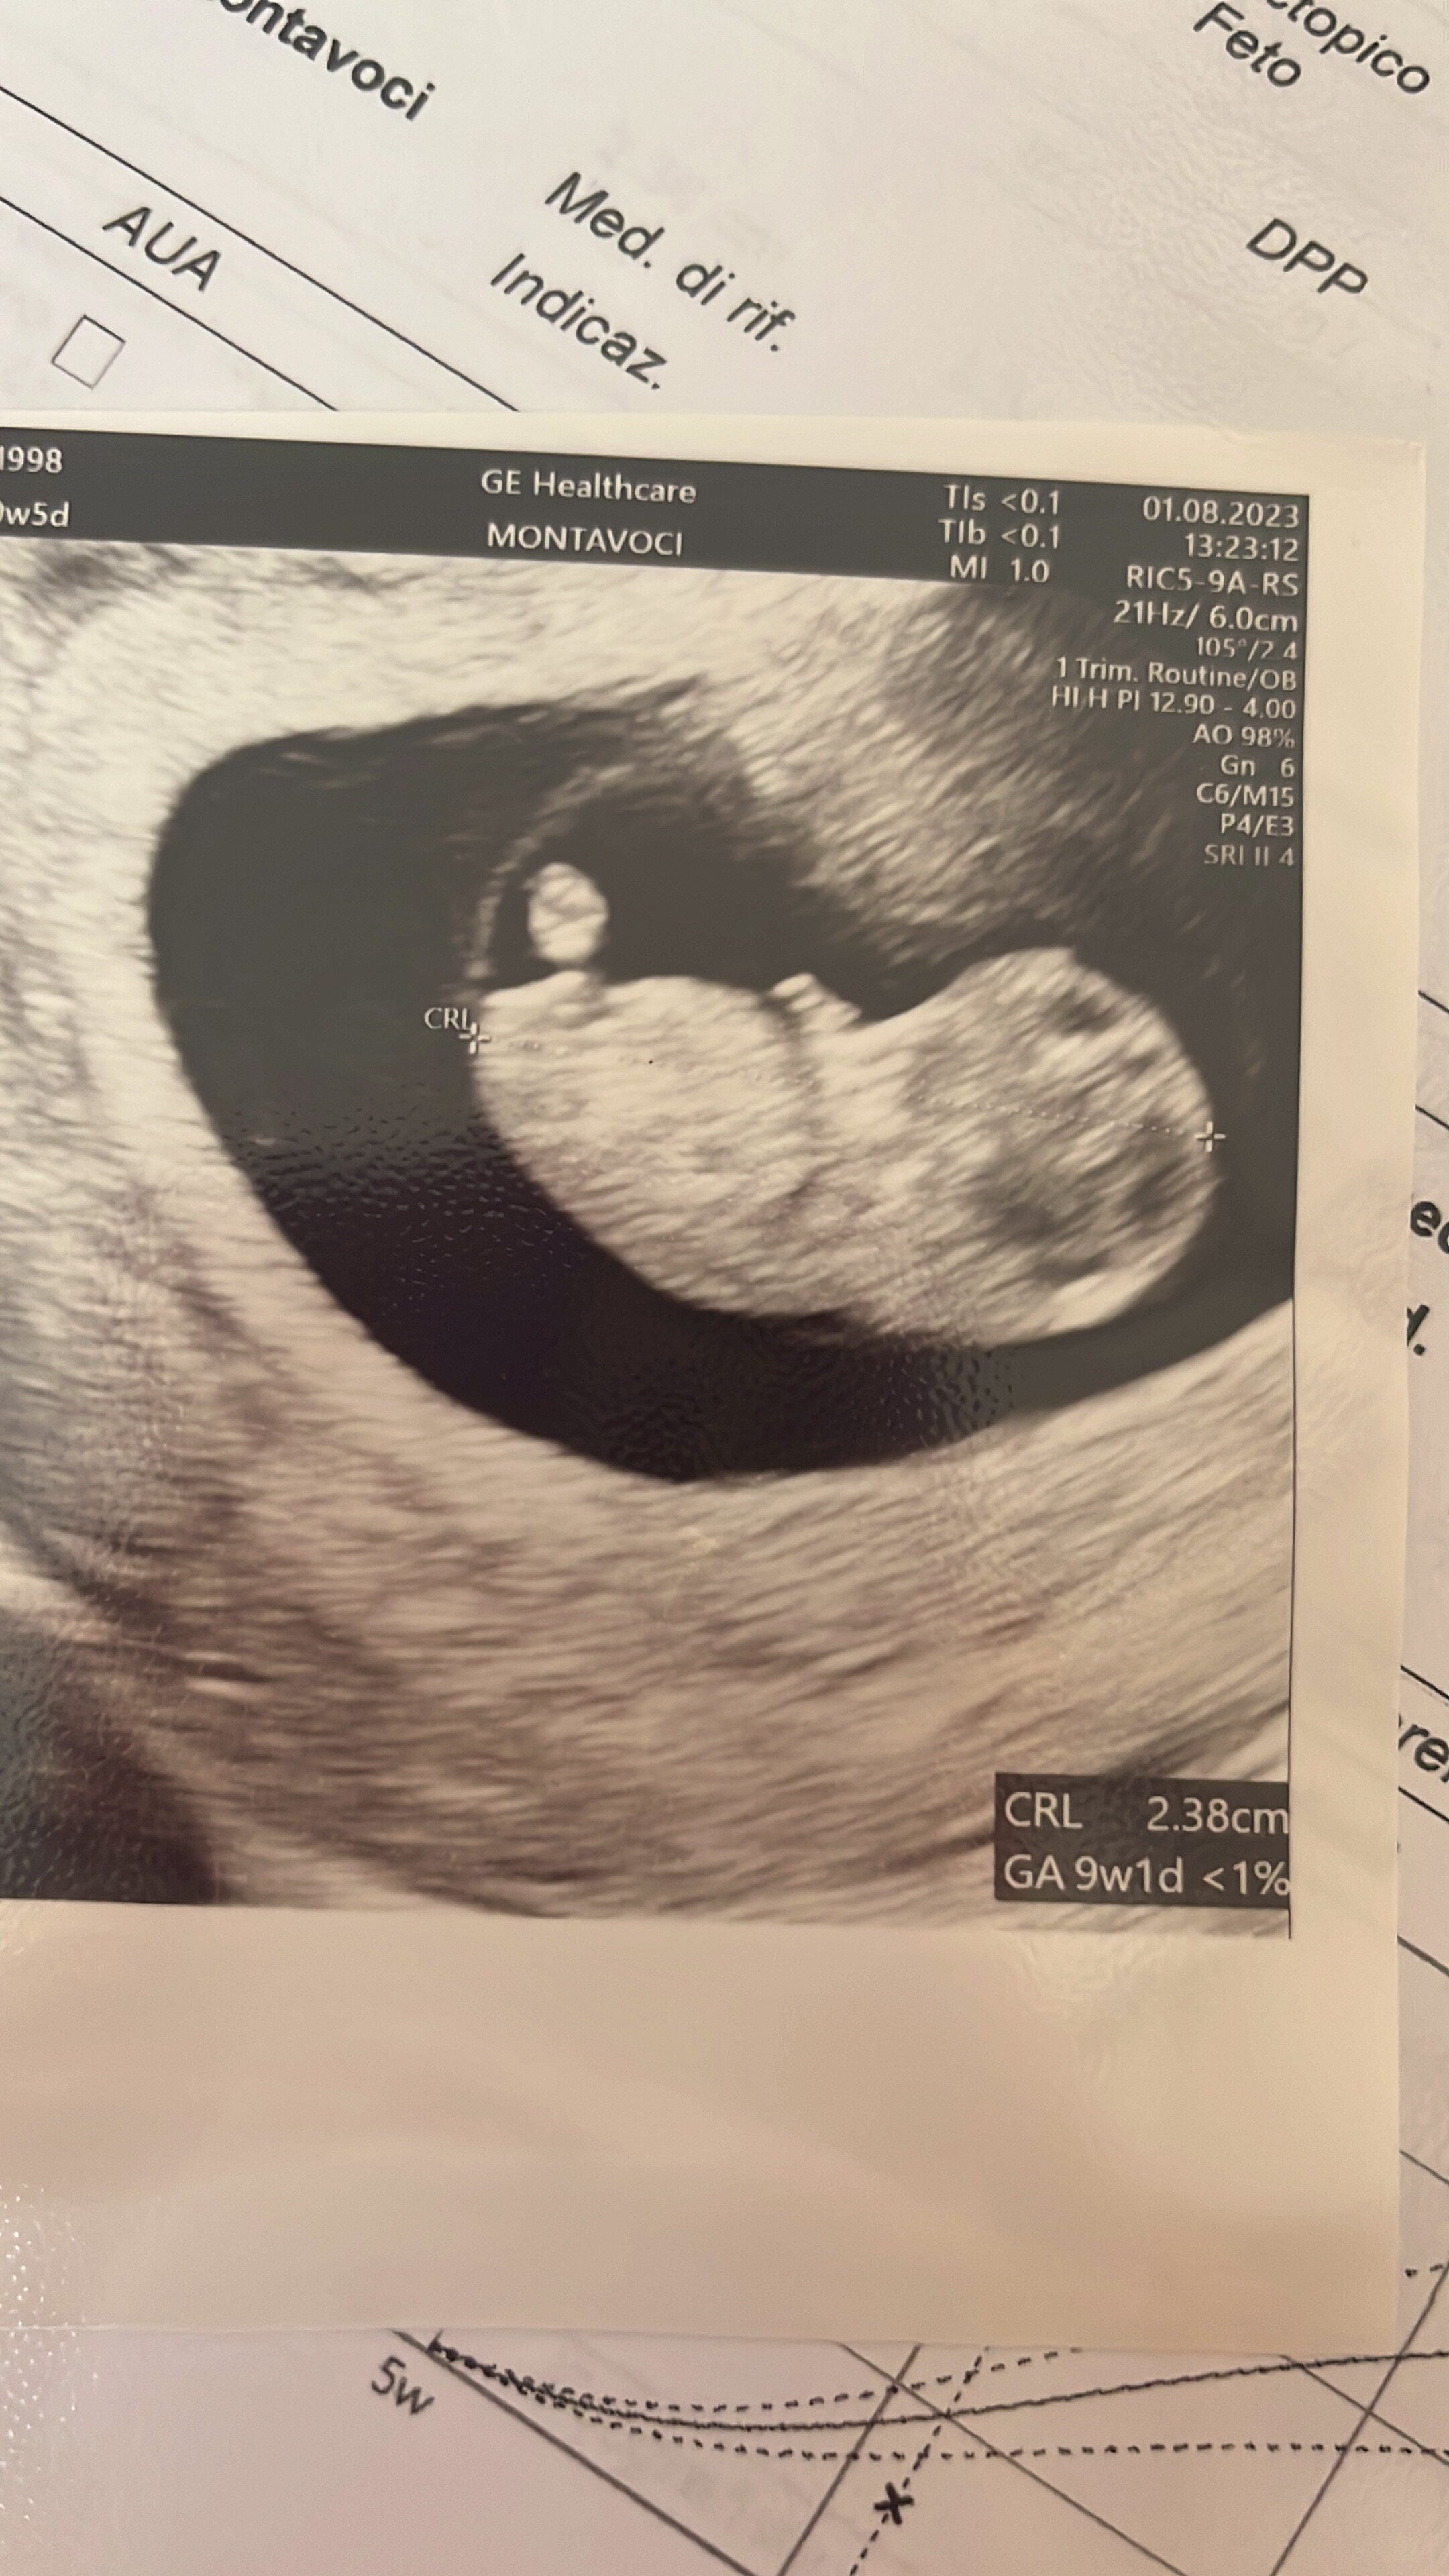

U nas dzisiaj tez było usg, zapomniałam napisać, ale również wszystko ok! Rośnie ładnie, serduszko bije! Jeszcze jakby mdłości troszkę odpuściły to dzień byłby lepszy😂Zobacz załącznik 1552887